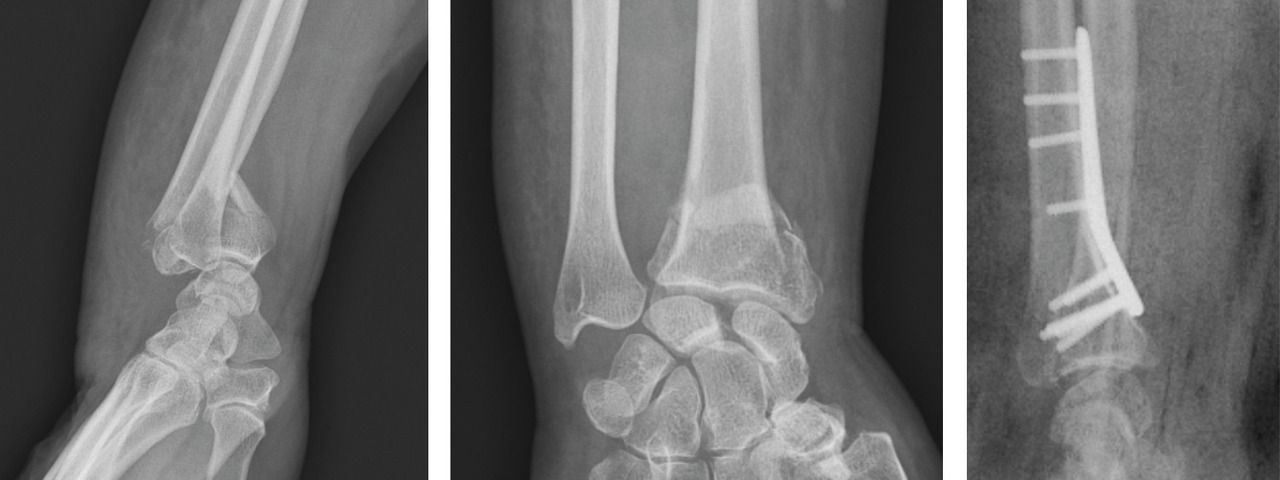

Les classifications lésionnelles utilisées à l’heure actuelle sont le fruit d’un processus de compréhension du traumatisme et de ses séquelles qui s’est échelonné sur plusieurs décennies. L’analyse de la fracture doit être focalisée sur les caractéristiques des 3 composantes anatomiques : métaphysaire, reliée au sens du déplacement fracturaire ; épiphysaire, reliée aux lésions articulaires ; et ulnaire, reliée aux lésions associées ostéoligamentaires.

Au niveau métaphysaire le déplacement peut être postérieur ou antérieur (fig. 6). En ce qui concerne le déplacement postérieur, il est important de se souvenir que la surface articulaire regarde vers l’avant. En d’autres termes, dès que cela n’est plus le cas, même si la surface articulaire n’est pas orientée vers l’arrière, il s’agit d’un déplacement postérieur. Classiquement, le déplacement postérieur est lié à un mécanisme dit en compression-­extension, c’est-à-dire une chute sur la main, le poignet étant en extension (fig. 7). Le déplacement est dit antérieur s’il y a une exagération de l’orientation antérieure de l’épiphyse radiale. Ce déplacement est classiquement lié à un mécanisme dit en compression-flexion, c’est-à-dire une chute sur la main, le poignet étant en flexion (fig. 7). La plupart du temps, ce déplacement postérieur ou antérieur s’accompagne également d’un déplacement externe, avec un tassement au niveau de la corticale latérale (fig. 8). Outre le déplacement antérieur, postérieur ou latéral, il est très important d’analyser au niveau du foyer de fracture métaphysaire l’importance de la comminution qui peut être uniquement postérieure, ou antérieure, ou circonférentielle, ce qui conditionne la stabilité de la fracture et oriente vers le type d’ostéosynthèse à réaliser.

Le traitement chirurgical, justifié en cas de déplacement non tolérable, repose sur 3 modalités pratiques distinctes : l’embrochage percutané, les plaques palmaires vissées, et le fixateur externe radiométacarpien, à ne jamais utiliser seul. Ces traitements remplissent le double rôle de réduction et de stabilisation de la fracture jusqu’à consolidation.

La mise en place des broches percutanées sont habituellement introduites dans le foyer de fracture, en arrière du radius, puis inclinées vers le bas pour réduire la bascule dorsale de la glène radiale et sont finalement fichées dans la corticale antérieure, épaisse, pour stabiliser la réduction obtenue. Il s’agit d’un embrochage « intrafocal » (dans le foyer de fracture). Une ou deux broches styloïdiennes dans le plan frontal complètent le montage. La bascule antérieure du fragment distal, la présence de refends articulaires, et la comminution métaphyso-épiphysaire sont indispensables à évaluer avant de proposer ce type de traitement et constituent des contre-indications relatives (fig. 12).

La mise en place de plaques palmaires nécessite un abord chirurgical antérieur et reste techniquement délicat, en particulier pour positionner la plaque en hauteur et pour la longueur des vis dont l’excès peut endommager les tendons extenseurs. L’indication phare reste les fractures métaphysaires à déplacement antérieur ou les comminutions métaphysaires étendues (fig. 13).

Enfin, le fixateur externe ne doit pas être utilisé seul car une traction excessive est un facteur de risque d’algo­neurodystrophie. Il doit être ajouté comme moyen de protection d’une ostéosynthèse par broche ou plaque précaire. Son rôle est de neutraliser les contraintes en compression sur l’extrémité inférieure du radius en cours de consolidation (fig. 14).